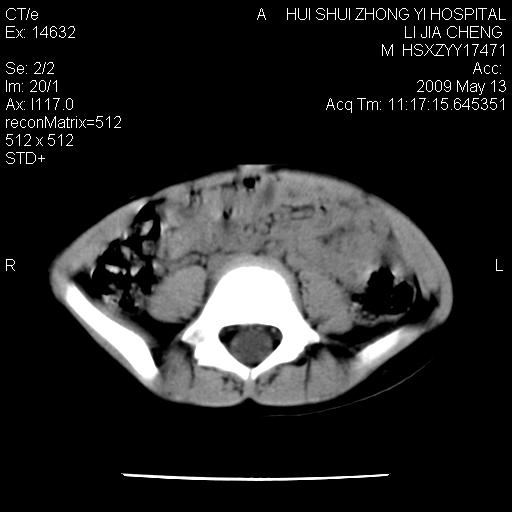

是不是有蛔虫哦,楼主图示块影前方肠管壁显著增厚,不除外慢性肠炎或肠壁占位,建议肠道准备后复查

肠道准备不足,im15---------------------18左侧腹腔病变?

肠管管壁均匀增厚,炎性可能

是小肠,壁稍厚可能是肠腔未很好充盈所致,腹部ct扫描未见明显异常。